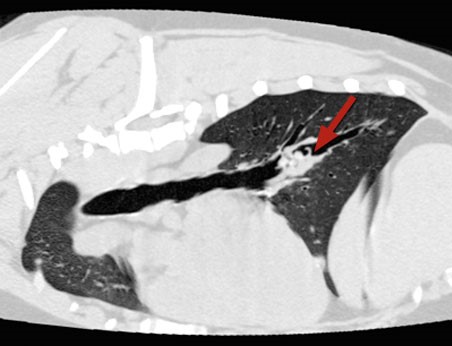

- Lungs are more complicated and may require specialist investigation and treatment in the form of a CT scan and removal using the flexible bronchoscope. Occasionally these cases may require major surgery to open the chest and remove an entire affected lung lobe

CT scans showing different views of the same dog’s chest with a grass seed lodged in the lungs (the grass seed is arrowed)